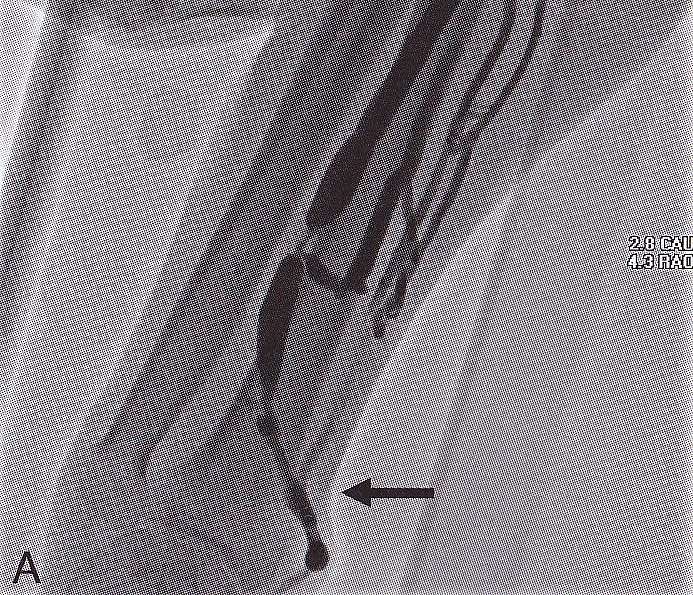

Circuit VesperⅡは、シャントPTAを中心とした教育・トレーニングおよびカテーテル評価を目的としたシミュレーターです。

あえて腕などの周辺構造を排除し、シャントPTAに集中できる設計とすることで、血管全体を立体的に、かつ目視で把握できる環境を整えました。

シャントPTA手技の全体像を立体的に観察できることにより、想定外の学習効果や、カテーテル性能の総合的な評価にもつながります。